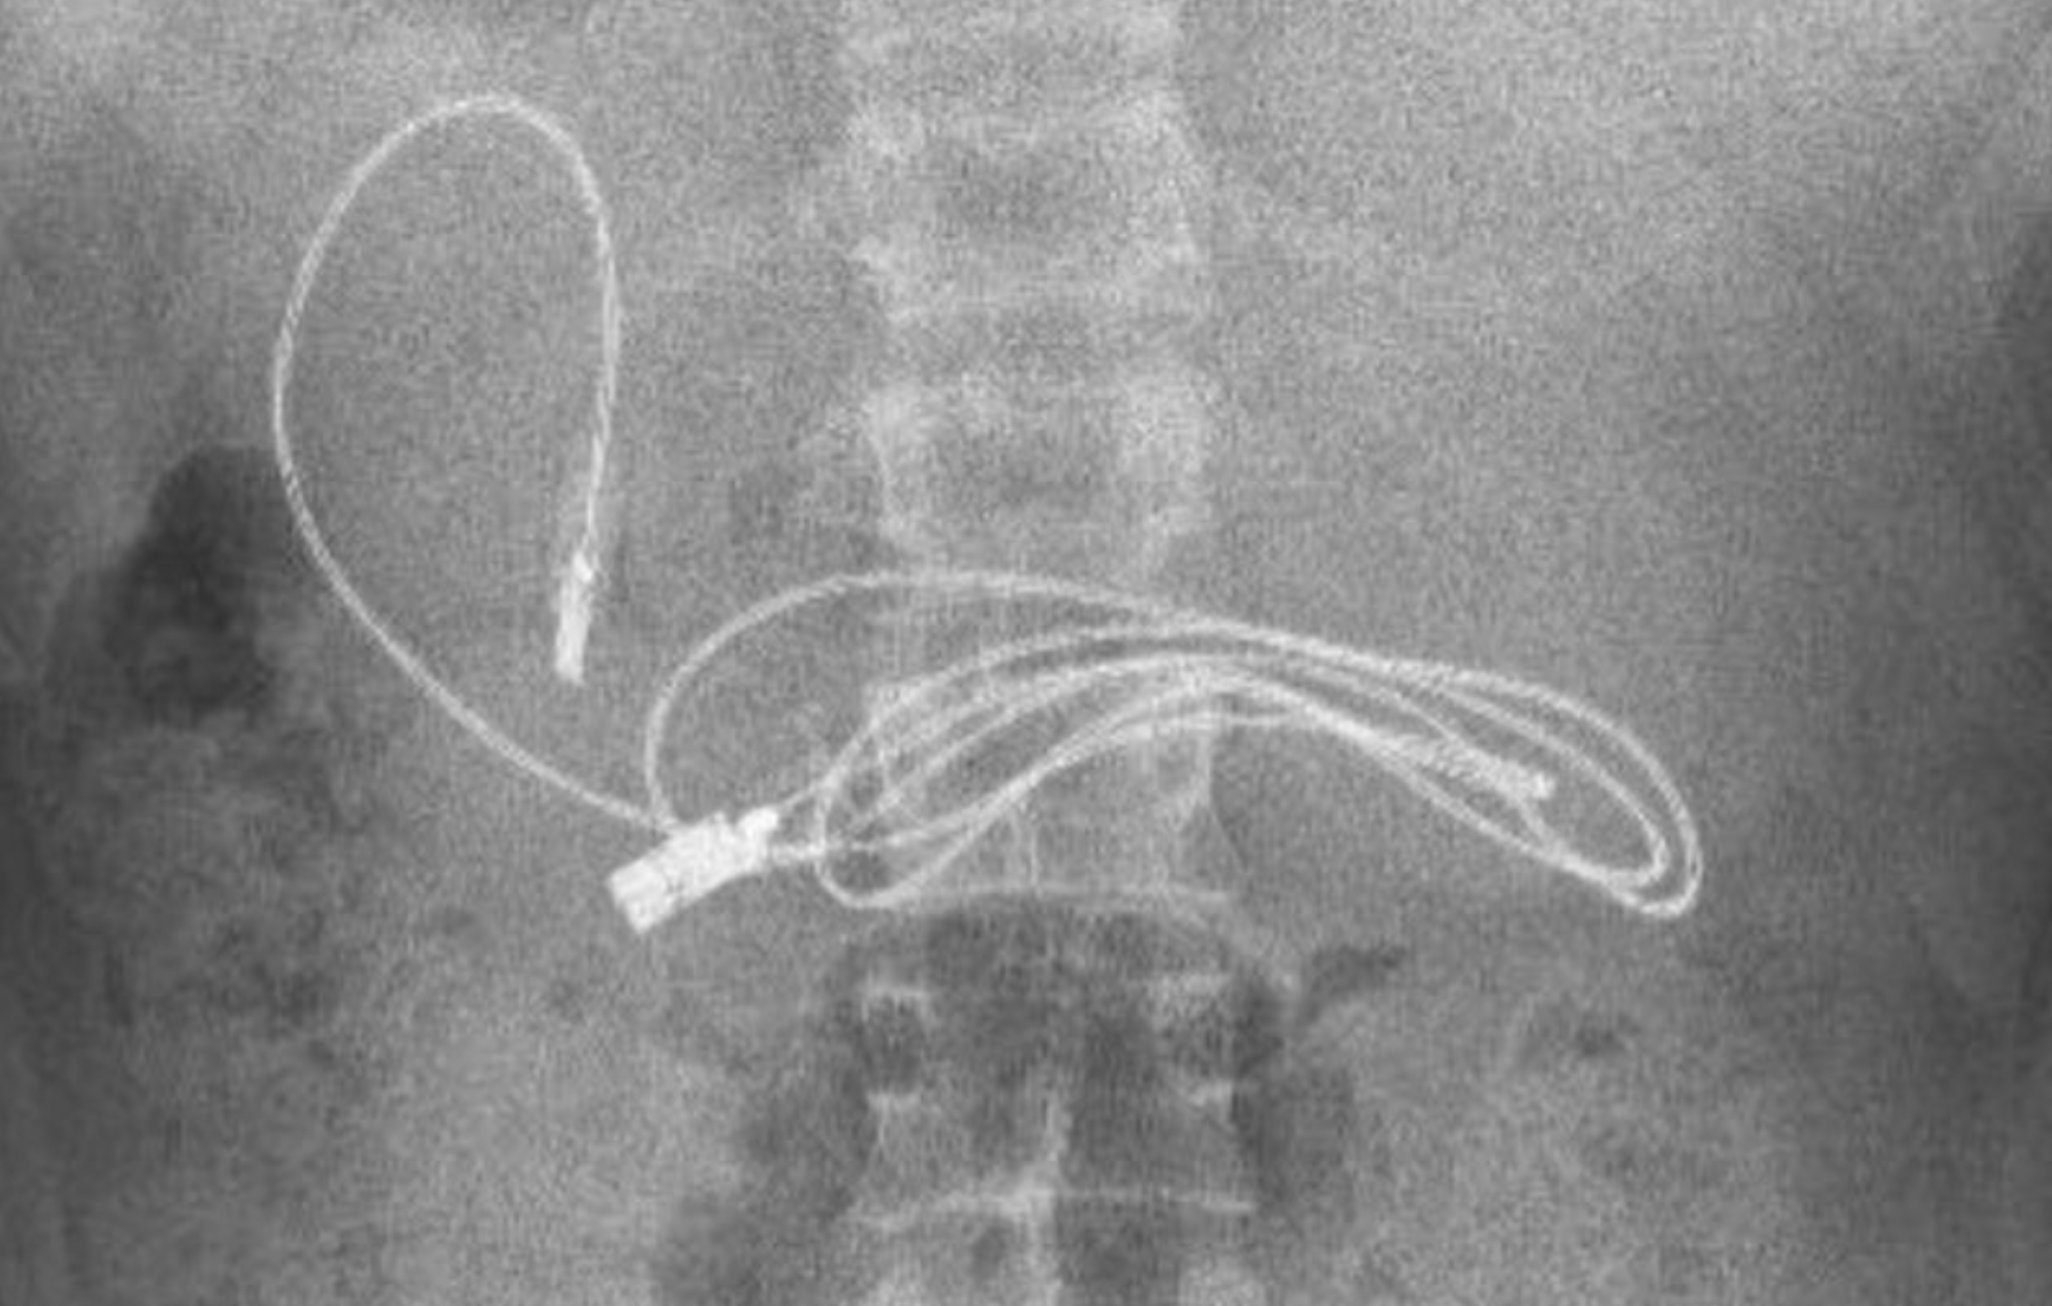

Se quedaron con la boca abierta cuando en la radiografía se podía divisar claramente estos dos objetos. De inmediato, el joven fue trasladado a un especialista, concretamente al hospital de Firat en Elazig, donde el jefe del departamento de gastroenterología, hepatología y nutrición pediátrica no podía creer que el menor tuviera en su interior semejantes objetos.

Ante esta situación, fue intervenido con el fin de extraer el cable y la goma lo antes posible. Los médicos han compartido en sus redes sociales la sorprendente radiografía y explicaron que el médico realizó una endoscopia a través de su boca para llegar al punto donde se encontraba el cable. Según recoge Telecinco, fue una tarea complicada porque uno de los extremos había pasado al intestino delgado.